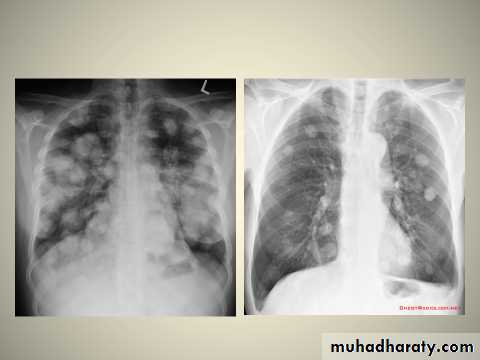

Secondary lung tumor:

Pulmonary metastases are common and the result of metastatic spread to the lungs from a variety of tumors and can spread via blood or lymphatics.1.Cannonball metastases refer to large well circumscribed, round multiple opacities like cannonballs

2.lymphangitis carcinomatosis , is the term given to tumor spread through the lymphatics of the lung , and is most commonly seen secondary to adenocarcinoma Unfortunately up to a quarter of patients with subsequently established lymphangitic carcinomatosis have normal chest x-rays . When abnormal the most common finding is of a reticulonodular pattern, with thickening of the interlobular septae which may resemble HYPERLINK "http://radiopaedia.org/articles/septal-lines-in-lung" Kerley B lines + /- pleural effusion .